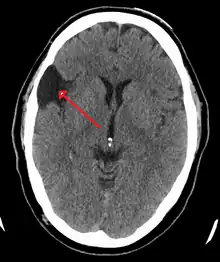

A CT scan of an arachnoid cyst | |

The diagnostic process typically begins with a medical history workup followed by a medical examination by a physician. Imaging tests, such as CT scans and MRIs, help provide a clearer picture. The physician typically looks for fluid (or other bodily substance) filled sacs to appear in the scans, as is shown in the CT scan of a colloid cyst. A primary health care provider will refer an individual to a neurologist or neurosurgeon for further examination. Other diagnostic methods include radiological examinations and macroscopic examinations. After a diagnosis has been made, immunohistochemistry may be used to differentiate between epithelial cysts and arachnoid cysts.[2] These examinations are useful to get a general idea of possible treatment options, but can be unsatisfactory to diagnose CNS cysts.[3][5] Professionals still do not fully understand how cysts form; however, analyzing the walls of different cyst types, using electron microscopes and light microscopes, has proven to be the best diagnostic tool. This has led to more accurate cyst classification and correct course of action for treatments that are cyst specific. In the past, before imaging scans or tests were available, medical professionals could only diagnose cysts via exploratory surgery.[2]